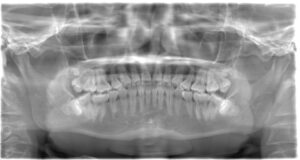

埋伏歯の抜歯

埋伏歯とは、歯が骨や歯茎の中に埋まってしまい、正常に生えない状態のことを指します。これらの歯は外科的な手術が必要になるため、難抜歯の代表的なケースです。